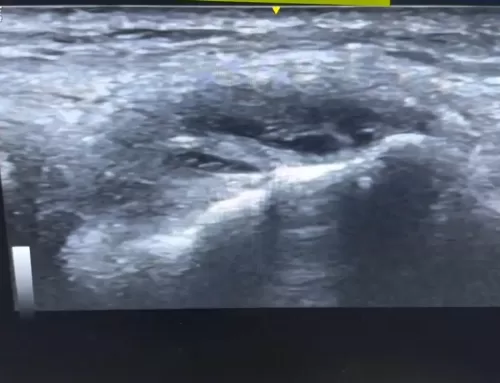

However, deeper ultrasound imaging reveals a prominent bony bump, known as insertional Achilles tendinopathy, which is the true source of the patient’s pain and swelling. The affected heel shows irregular bone structure, hypoechoic (dark) areas, and localized inflammation right at the pain point.

The comparison with the other (non-painful) side shows only minor tendon changes, confirming that the extra bone and tendon irregularity at the insertion point is the root cause of discomfort. This video is a great resource for understanding less obvious causes of heel pain and how ultrasound imaging can reveal hidden structural issues often missed in a surface-level exam.